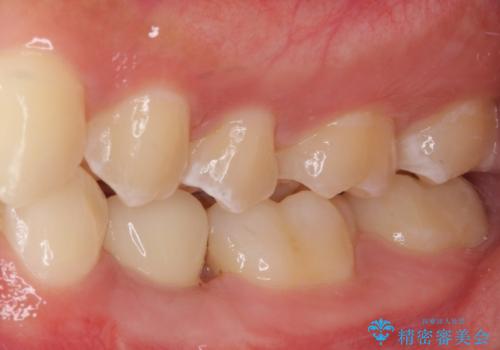

矯正治療が終わるタイミングに合わせてインプラントの埋入を行っていたので、矯正治療を終了すると同時にセラミック補綴治療を行えました。

短期間でしっかりと治療を終えることができました。